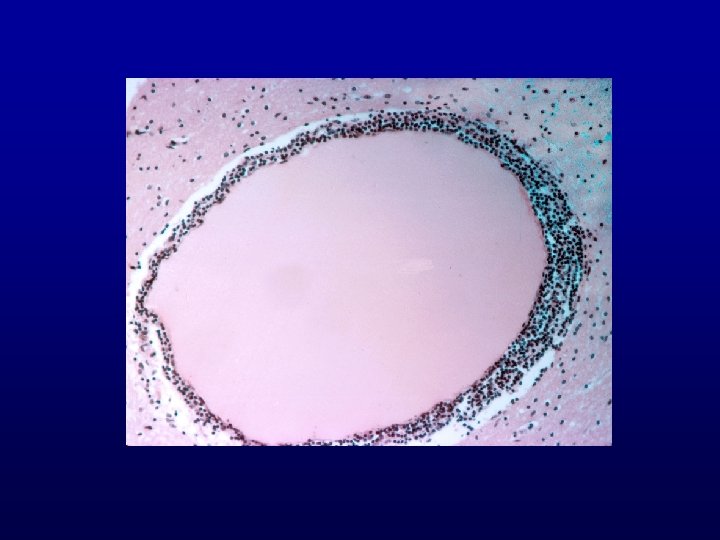

Encysted metacestode

A cysticercus cyst of the brain. Cysticercosis is caused by ingestion of poorly cooked pork containing the eggs of the tapeworm Taenia solium. Man is an intermediate host in which the larval worms migrate to a variety of tissues, including brain, and encyst. Such cysts are a cause for seizures.